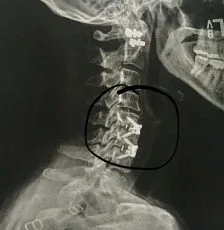

An MRI is used to make the final diagnosis and confirm the need for surgery. Once under general anesthesia, a 1-2 inch incision is made in the front of the neck. The damaged disks are removed and replaced by a neurosurgeon or orthopedic surgeon. (or, in my case, a team consisting of both) Various materials (mine a special glue comprised of finely ground cadaver bone; allograft) allow regeneration and formation of new bone. The process completes the fusion and stabilizes it with interbody spacers. The vertebrae are held together with cages and screws, like the model shown below and in my X-ray images.

I arrived at 5:00 am at the surgery center and prepared for a four-hour procedure. I suffered from narrowing (stenosis), disk degeneration of C 4-5-6, radiculopathy (compressed nerve roots), and bone spurs. Two surgeons worked together, with the orthopedic surgeon operating on the bones and the neurosurgeon repairing the damaged nerves. The surgeon said if I didn't proceed with the surgery, there was a possibility I could become paralyzed if there was ever a severe collision or accident. The choice to continue was a no-brainer, and I'd be able to return to most, if not all, of my activities in 6-12 months. (marathon running, backpacking, yoga)